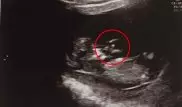

На снимке эмбриона нашли ангела-спасителя На снимке эмбриона нашли ангела-спасителя Ребенок родился со здоровым весом в 3,15 килограмма, несмотря на то, что в утробе его шею обвернула пуповина.